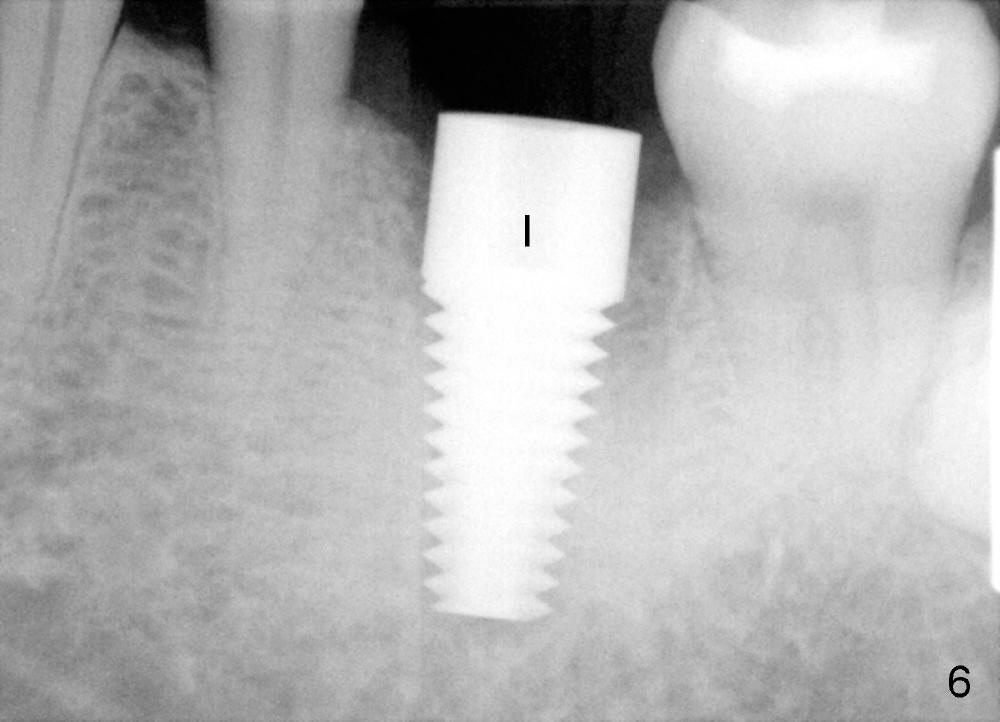

A 41-year-old man has discomfort in the lower left 1st molar. Exam shows swelling and a fistula in the mesiobuccal gingiva (Fig.1 >) and large radiolucency around the mesial root (Fig.2 *). After extraction and thorough debridement, osteotomy is initiated in the mesial socket, but the upper portion of the reamer (Fig.3 R, 2.5 mm) is placed in the middle of the edentulous space. By the time 5 mm reamer is removed, the osteotomy (Fig.4 O) forms mainly in the mesial socket with the septum (S) deviated to the distal socket. A 7x17 mm tap is placed with stability (Fig.5 T). An implant with the same dimension is placed with insertion torque more than 60 Ncm (Fig.6 I). With the large implant, two proximal sutures are able to close the remaining socket gaps (Fig.7). The swelling and fistula disappears and the gingiva tightly surrounds the implant in 1 week postop (Fig.8).